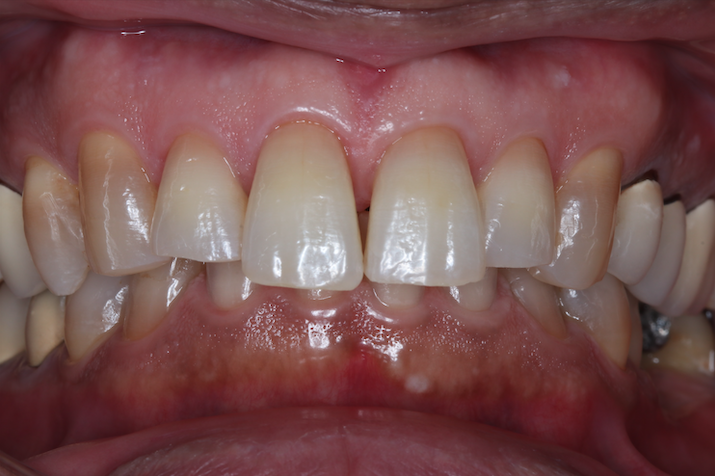

症例①

年齢40代女性

治療期間1ヶ月

治療内容セラミック治療、インプラント治療、ホワイトニング

治療箇所セラミック:左上1番、2番 左下5番、7番 右上1番、2番、3番、4番、5番 右下5番、6番、7番

インプラント:左下6番

治療費用500,000円